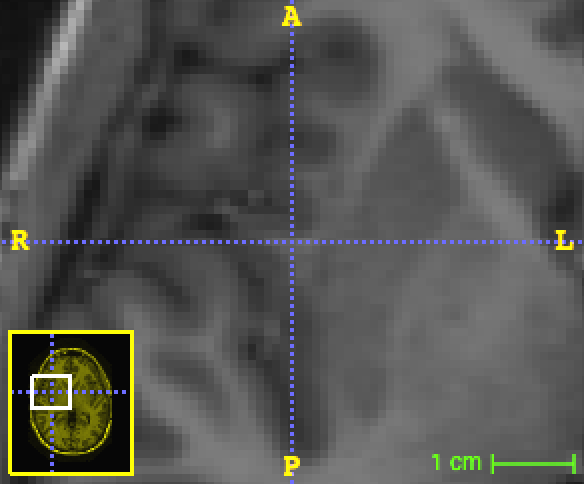

Refer to caption

(a) 29×29292929\times 29 patches (b=29𝑏29b=29).

(b) 87×87878787\times 87 original patches downscaled into 29×29292929\times 29 patches (c=29𝑐29c=29, s=3𝑠3s=3).

Figure 4: Example of random 2D patches from the MICCAI dataset.